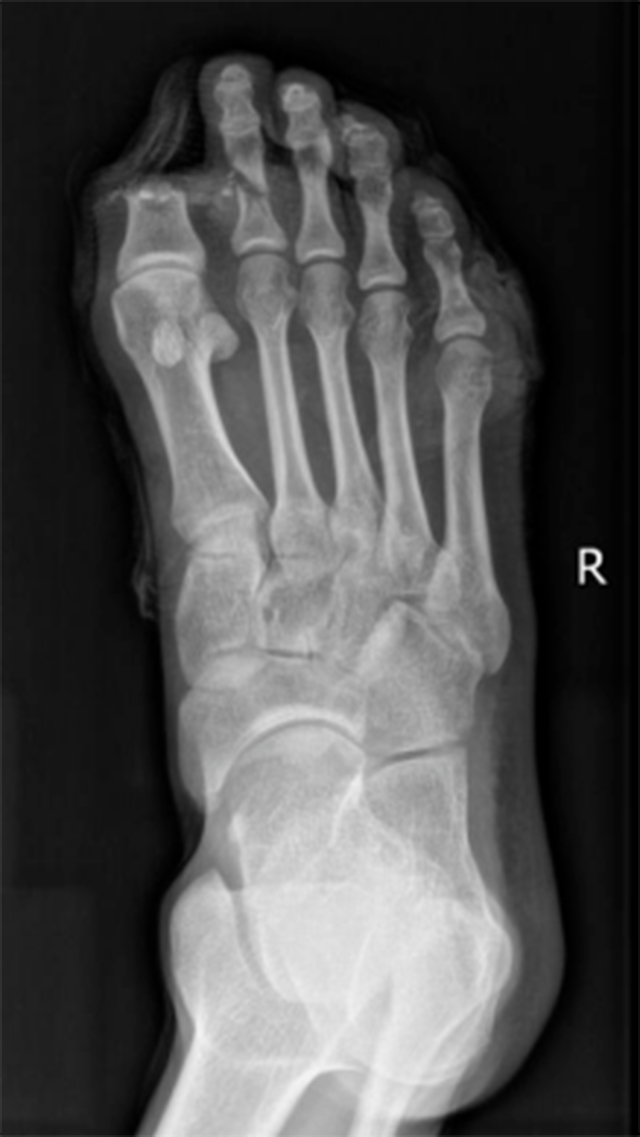

周末一大早,30岁的小李在家中用切割机锯木条。为了稳定木块,小李右脚用力踩着木块。突然,锯条断裂,锋利的锯条瞬间将小李右脚大拇趾切断,第二根脚趾被切了一半,剩下一半还悬在脚上,疼痛剧烈、出血不止,家人赶紧用毛巾止血,用口袋把断掉的大拇趾装好,将小李送到附近医院。

医院接诊后,立即为小李清创、止血、包扎,并建议小李立即到大医院进行断趾再植。于是家人带着小李立即驱车来到了西南医科大学附属中医医院骨伤科手外・儿骨・烧伤整形组。

黄宇主治医师接诊后,立即组织了科室专家会诊,并将小李断掉的大拇趾放进4℃的冰箱保存。“通常断趾在没有血供的情况下,常温只能保存8小时左右。”科室主任陈孝均副教授说。

从小李受伤送到医院,已经过去了5个小时。事不宜迟,必须立即进行断趾再植手术。于是,陈孝均副教授、医疗组长刘安铭副教授、黄宇主治医师等共同为小李制定了急诊手术方案,由黄宇主治医师主刀。